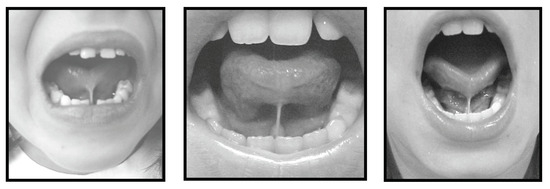

Following the classification of the frenulum as normal or altered, four measurements were obtained using the digital Starret slide caliper. All measurements were taken by a single speech therapist. The recorded measurements included: a) maximum mouth opening (with no tongue interference) as measured at the incisal edges of the left upper and lower central incisors. This measurement served as a reference support point for the slide caliper (Figure 4), and was taken as an absolute value reference for subsequent comparison with other measurements; b) for the second measurement each subject was requested to put the apex of his/her tongue on the palatine (incisal) papilla, maintaining this posture with the mouth open maximally and with the support points for the slide caliper maintained at the left central incisors (Figure 5); c) the third measurement was obtained while the subject created a negative pressure by sucking the tongue against the hard palate area, maintaining this position with the mouth open (Figure 6); d) the last measurement was taken while each subject protruded the tongue and stretched it maximally over a wooden spatula held by the examiner at the lower incisors (Figure 7). A mark made with a black pencil was recorded on the spatula at the place of the longest measurement of the tongue. Using the slide caliper, this measurement, from the tip of the spatula to the place where the tongue had reached in extension was measured (Figure 8). All measurements were logged onto a previously designed table consisting of the following data: initials of subject’s name and age, collection date, classification of frenulum as normal or altered, the measurements taken at full mouth opening, tongue on the papilla, tongue sucked against the hard palate, and tongue on the spatula. The rule of three was applied, comparing the wide-open mouth reference valus with each of the other three measurements. The data were collected between the months - August 2002 to December 2003.

Figure 4. Full Mouth Opening.

Figure 5. Tongue on the Papilla.

Figure 6. Tongue Suctioned on the Hard Palate.